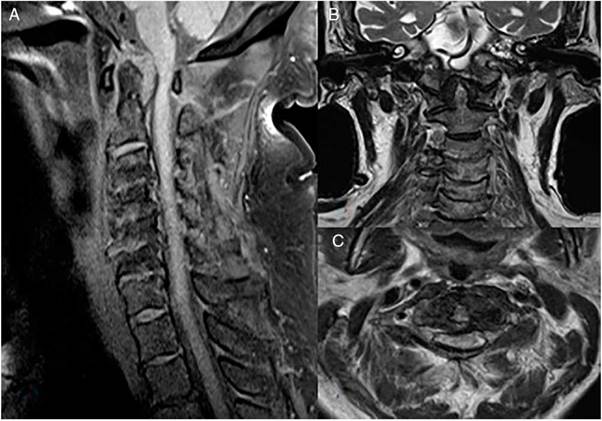

Paciente masculino de 80 años, hipertenso y fumador de larga data. Presenta síntomas de 5 meses de evolución consistentes en parestesias e hipoestesias en dedos de las manos y antebrazos. Progresivamente aparición de disestesias en miembros inferiores e imposibilidad para la marcha por debilidad. En el transcurso de 2 meses estado de postración y dependiente para todas las actividades de la vida diaria. Presentó caída, por lo que es remitido a hospital de cuarto nivel. Al examen físico con cuadriparesia espástica simétrica, hiperreflexia generalizada, Babinski bilateral, hipoestesia generalizada con nivel sensitivo C3, Hoffman bilateral. La resonancia magnética (RM) simple de columna (fig. 1) evidenció pannus odontoideo que ocasiona un canal estrecho adquirido con estenosis severa de la amplitud del canal raquídeo y compresión de la médula espinal con signos de mielopatía aguda. Otros hallazgos incluyeron edema de la médula espinal en su porción cervical así como cambios degenerativos en todos los segmentos de la columna cervical. En los análisis de laboratorio se observó factor reumatoide positivo (113 UI/ml), antipéptido cíclico citrulinado negativo (4,1 U/ml), reactantes de fase aguda (velocidad de sedimentación globular, proteína C reactiva) y anticuerpos antinucleares negativos. La radiografías de manos y pies sin erosiones óseas, con cambios osteoartrósicos. Se realizó descompresión y artrodesis C1-C2 con buena evolución posoperatoria y recuperación parcial del déficit motor. Tres semanas posteriores al ingreso, se da alta con tratamiento con prednisolona 10 mg, sulfasalazina 1.000 mg y leflunomida 20 mg al día con mejoría clínica dado por caminata sin ayuda.

Las imágenes son muy importantes para evaluar el compromiso axial por AR. La radiografía de columna cervical es útil en pacientes asintomáticos. Las proyecciones dinámicas son requeridas para observar subluxaciones, sin embargo, no visualiza anormalidades de tejidos blandos que puedan comprometer el canal espinal, como en nuestro paciente con mielopatía por pannus. Esta desventaja la comparte con la tomografía computarizada, por lo que la RM es la modalidad de imagen de elección para los pacientes sintomáticos debido a la capacidad para detectar anomalías en los tejidos blandos y la médula espinal[4].